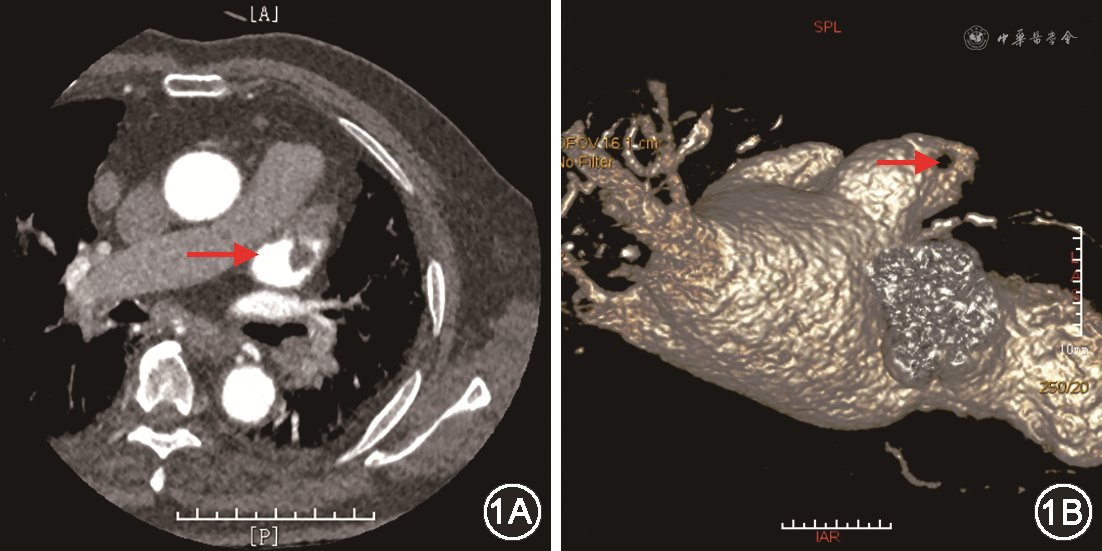

患者男,83岁,主因“反复心悸10余年,再发2 d伴头晕”于2019年8月14日入院。患者有长程持续性心房颤动(房颤)病史10余年,未曾服用抗凝药物。2019年7月7日患者因胸闷心悸伴气短就诊,心电图示房颤伴快速心室率。既往有反复脑梗死、冠心病、高血压、糖尿病、肾功能不全病史。实验室检验结果:空腹血糖9.00 mmol/L(参考值4.10~5.90 mmol/L),尿素氮13.00 mmol/L(参考值2.50~6.10 mmol/L),肌酐159 μmol/L(参考值46~92 μmol/L),N末端B型利钠肽原1 514 ng/L(参考值0~125 ng/L),甲状腺功能正常。经胸超声心动图:左心房前后径48 mm,上下径80 mm,左右径50 mm,轻度二尖瓣反流,主动脉瓣钙化伴轻度反流,左心室射血分数65%。头颅CT平扫:脑内多发腔隙性梗死(部分陈旧)及缺血灶,右侧颞枕顶软化灶;老年脑改变。心脏CT血管成像(CTA):左心耳底部局部充盈缺损,提示左心耳血栓形成(图1)。予华法林2.5 mg(每日1次)口服,调整国际标准化比值(INR)2~3。患者未定期复查INR,后因反复胸闷心悸不适,于8月14日再次入院。经食道超声心动图(TEE):左右心房血液瘀滞,左心耳更明显,并见20.0 mm×7.0 mm低回声团,无明显活动度,蒂位于心耳上壁偏前近心耳尖部(图2A)。诊断:长程持续性房颤,纽约心脏病协会(NYHA)心功能Ⅱ级,左心耳血栓,冠心病,高血压,陈旧性脑梗死,2型糖尿病,肾功能不全。CHA2DS2-VASc评分8分,HAS-BLED评分3分。

经讨论决定行左心耳封堵术。经股动脉路径将EZ血栓保护系统H74920100-1900(波科国际医疗贸易上海有限公司)送至左、右侧颈内动脉,房间隔穿刺成功后予以肝素钠监测激活凝血时间(ACT)250~350 s之间。交换送入LAmbre[先健科技(深圳)有限公司]输送外鞘及猪尾造影导管,调整至心耳开口,造影显示左心耳呈菜花形,测左心耳开口直径为30 mm,内口直径为24 mm。输送内鞘抵左心耳口部,选用LAmbre封堵器型号为LT-LAA-2832,于左心房心耳口外打开封堵器固定盘,推送至心耳内锚定,血栓随固定盘推入左心耳底部,然后回撤外鞘,在左心耳开口外打开密封盘。复查左心房造影和TEE,见封堵器位置合适,伞周上缘偏前见约2 mm残余分流;左心房及封堵伞周围未见异常回声,牵拉稳定,对周围结构无影响,缓慢释放封堵器(图2B)。术后予华法林抗凝,初始剂量为1.875 mg(每日1次),调整INR 2~3。左心耳封堵后8周复查TEE,示封堵器位置良好,伞周上缘、上缘偏前均见约1 mm残余分流,密封盘伞面上侧见18.0 mm×6.0 mm低回声团块。抗凝治疗方案改为利伐沙班联合氯吡格雷。左心耳封堵后16周再次复查TEE,示左心房内明显血流瘀滞,密封盘伞面见混合回声团块18.0 mm×2.5 mm,左心房部分稍高回声,伞面部分低回声,考虑血栓机化;密封盘上缘,上缘偏前,及后缘偏下见1.5、1、1 mm残余分流(图2C)。抗凝治疗方案改为阿司匹林联合氯比格雷,密切随诊,患者一般状况稳定。左心耳封堵后12个月复查TEE,提示封堵器位置良好,密封盘伞面9-12点范围见33.0 mm×10.0 mm低回声团块,密封盘上缘、上缘偏前见2处1 mm残余分流(图2D)。予阿司匹林(100 mg,每日1次)联合华法林(2.5 mg,每日1次)长期口服,调整INR 2~3。随诊12个月,患者生活质量可,未发生心脑血管事件。

本例的左心耳血栓位于左心耳中-尖部,适合采用左心耳封堵治疗。患者因肾功能不全,左心耳封堵术后采用华法林抗凝,术后8周见器械相关血栓形成(device-related thrombus,DRT),故强化抗栓方案(利伐沙班联合氯吡格雷),16周后复查TEE见血栓机化。患者及家属强烈要求停用抗凝药物,故谨慎改为双联抗血小板药物。术后1年复查TEE,再次出现左心耳血栓。考虑患者高龄,合并心肾功能不全,且住在养老院复查TEE存在困难,故续予华法林联合阿司匹林治疗,随诊1年无出血及缺血性卒中等并发症。